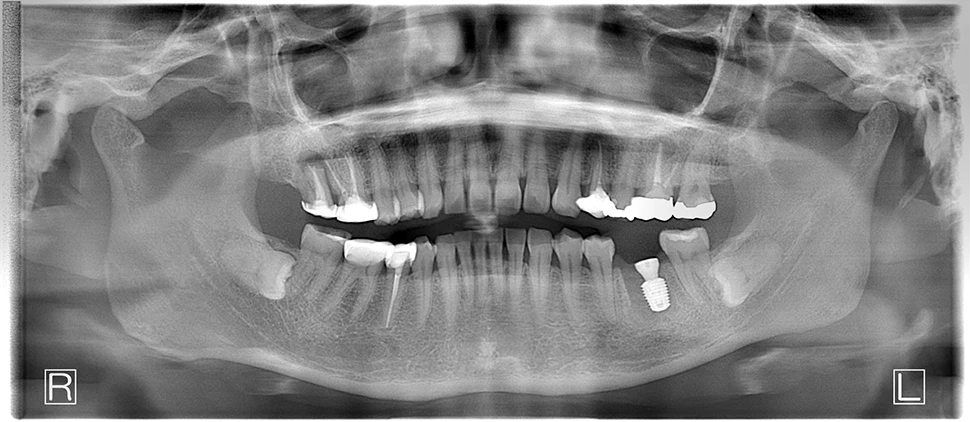

40代、女性、左下噛むと痛いこと主訴に来院され、インプラント治療を行いました。

| 診断結果 | 左下6番歯根破折 |

| 治療内容 | 抜歯即時インプラント |

| 治療期間 | 8週間 |

| 治療費用 | ¥539,000(税込) |